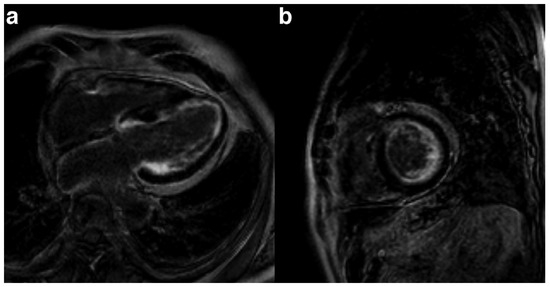

The Eustachian ridge is ablated as part of the cavotricuspid isthmus (CTI) involved in typical atrial flutter (AFL) ablation, but is itself rarely an arrhythmogenic focus. We report a case of a patient with dual tachycardia involving the CTI area....